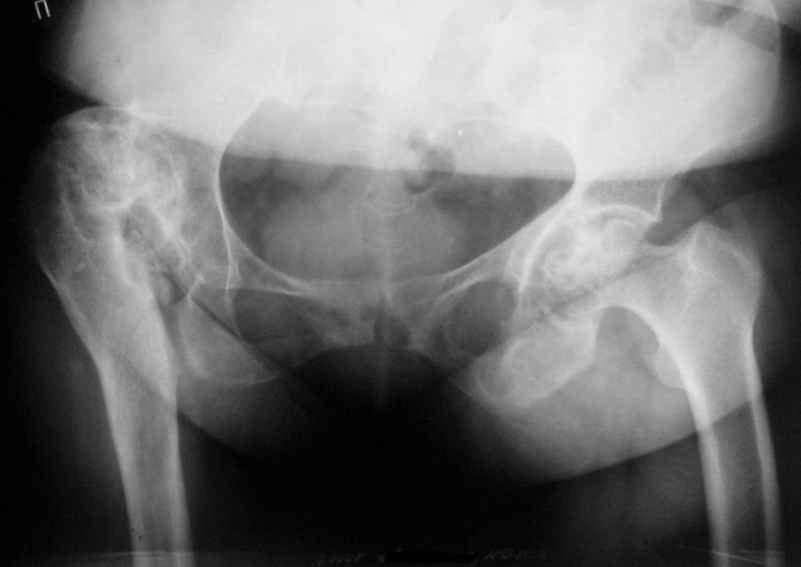

Уважаемые коллеги! Хотелось бы услышать Ваше мнение относительно тактики лечения данной пациентки. Пациентка 1953 г.р. поступила в клинику с диагнозом: "Деформирующий артроз в неоартрозе III ст. между головкой правого бедра и правой подвздошной костью, исход открытого вправления врождённого вывиха правого бедра. АВНГБ слева III-IV ст., коксартроз слева IIIст.Остеобластокластома левой седалищной кости."Из анамнеза: в возрасте 14 лет - открытое вправление врождённого вывиха правого бедра. В 1980 г. остеотомия, дистракционный остеосинтез правой бедренной кости.Зимой 2003г. обнаружена ОБК левой седалищной кости, получила курс лучевой терапии. В настоящее время данных за прогрессирование патологического очага нет. Пациентка поступила для эндопротезирования правого тазобедренного сустава. Учитывая наличие вальгусной деформации правого бедра и костей правой голени, возник вопрос, что выполнять в первую очередь - эндопротезирование, или же корригирующие остеотомии с исправлением оси конечности? Мнения коллег разделились.Заранее благодарны за помощь.

С отведением у пациентки проблемы - 0 град., приведение до 30 град, сгибание/разгибание=140/150 град., внутр. ротация 0 град., наружная ротация 20 град. Относительное и ортопедическое укорочение правой нижней конечности всего 1 см.(в 1980г. удлинение правого бедра на 4 см.). Имеются признаки остеохондроза дисков поясничного отдела позвоночника.

Учитывая отсутствие выраженной фиксированной приводящей контрактуры, рассматривали вариант первичной коррекции вальгусной деформации конечности.

Второй рассматриваемый вариант - эндопротезирование правого тазобедренного сустава с низведением и коррекцией деформации на уровне проксимального отдела бедра. Вторым этапом - коррекция вальгусной деформаци голени.

Вариант одномоментной установки эндопротеза и коррекции осевой деформации нижней конечности представляется нам действительно агрессивным вмешательством.